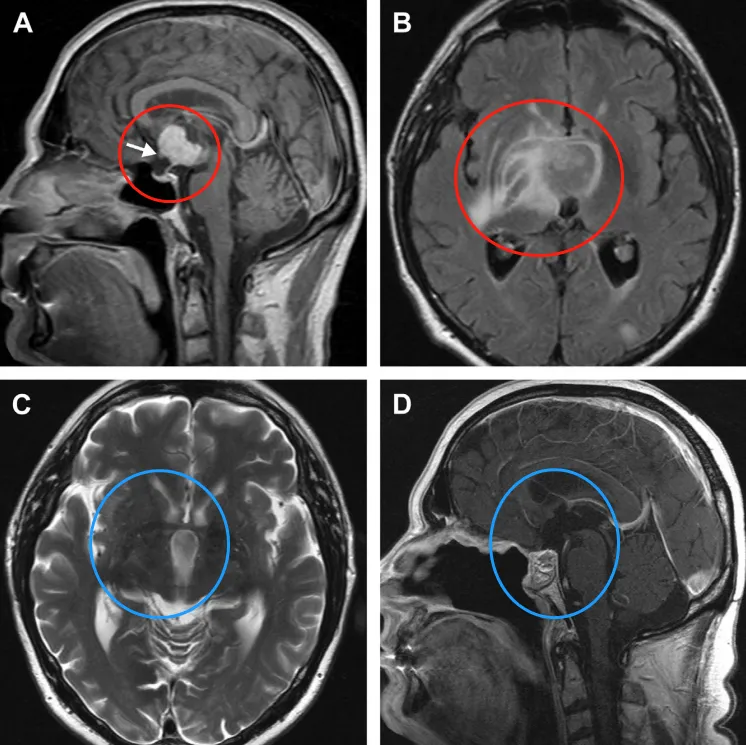

儿童颅咽管瘤的治疗目标到底是追求全切还是功能保留?目前医学界的普遍看法是,应该更侧重于患儿的生活质量而非肿瘤的根治性切除,因此,通常会建议次全切除加放疗的治疗模式,从而避...

颅咽管瘤作为儿童常见的颅内先天性肿瘤之一,它的治疗可能会引发多种并发症,手术可能因直接组织操作或缺血而损伤神经结构,放疗则可能引起放射性坏死或血管病变。手术的成功只是小儿...

在儿童神经外科领域,造釉细胞瘤性颅咽管瘤(AC)是个特殊的狠角色它虽被归为低级别恶性肿瘤,却因紧邻视路、垂体、下丘脑等关键结构,让治疗陷入两难:彻底切除可能导致终身内分泌紊...